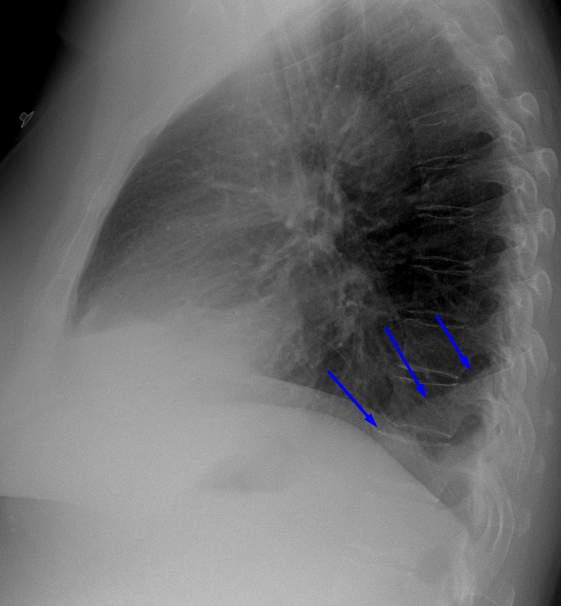

Age: 55

Sex: Female

Indication: Hemoptysis

Sample ReportRight middle and lower lobe collapse. Recommend chest CT to assess for a central obstructing mass.